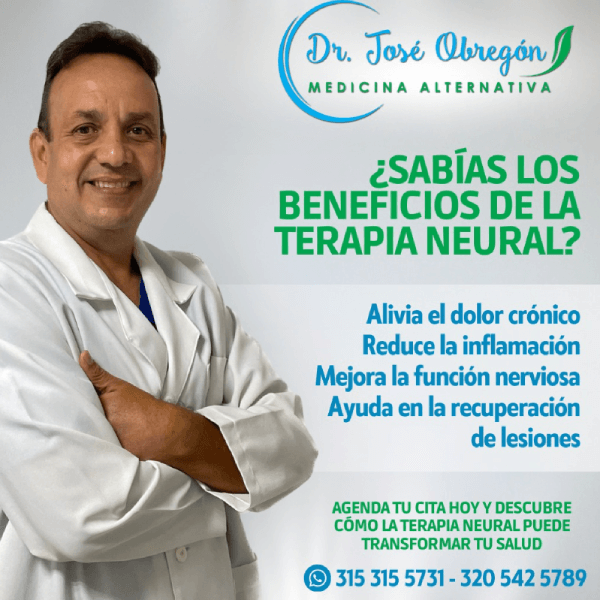

Acerca de Dr. José Antonio Obregón Jánica

Doctor José Antonio Obregón Jánica médico especializado en Medicina Alternativa en la Universidad Nacional de Colombia.

Con su experiencia de 32 años realiza tratamientos relacionados con naturopatía, terapia que estimula la capacidad curativa del cuerpo humano.

En su especialidad realiza tratamientos de terapia neural, homeopatía, homotoxicología, terapia de quelación endovenosa, terapia de regeneración articular con plasma rico en plaquetas